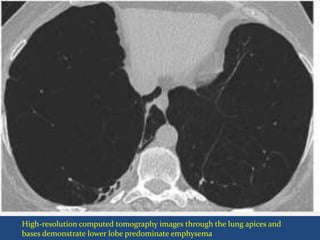

High-resolution computed tomography images through the lung apices and

bases demonstrate lower lobe predominate emphysema

Lower-lung predominance, and vascular attenuation are better shown by the coronal

minimum intensity projection and maximum intensity projection images .

High-resolution computed tomographyimages through the lung apices and bases demonstrate lower lobe predominate emphysema

• 64.

Lower-lung predominance, andvascular attenuation are better shown by the coronal minimum intensity projection and maximum intensity projection images .